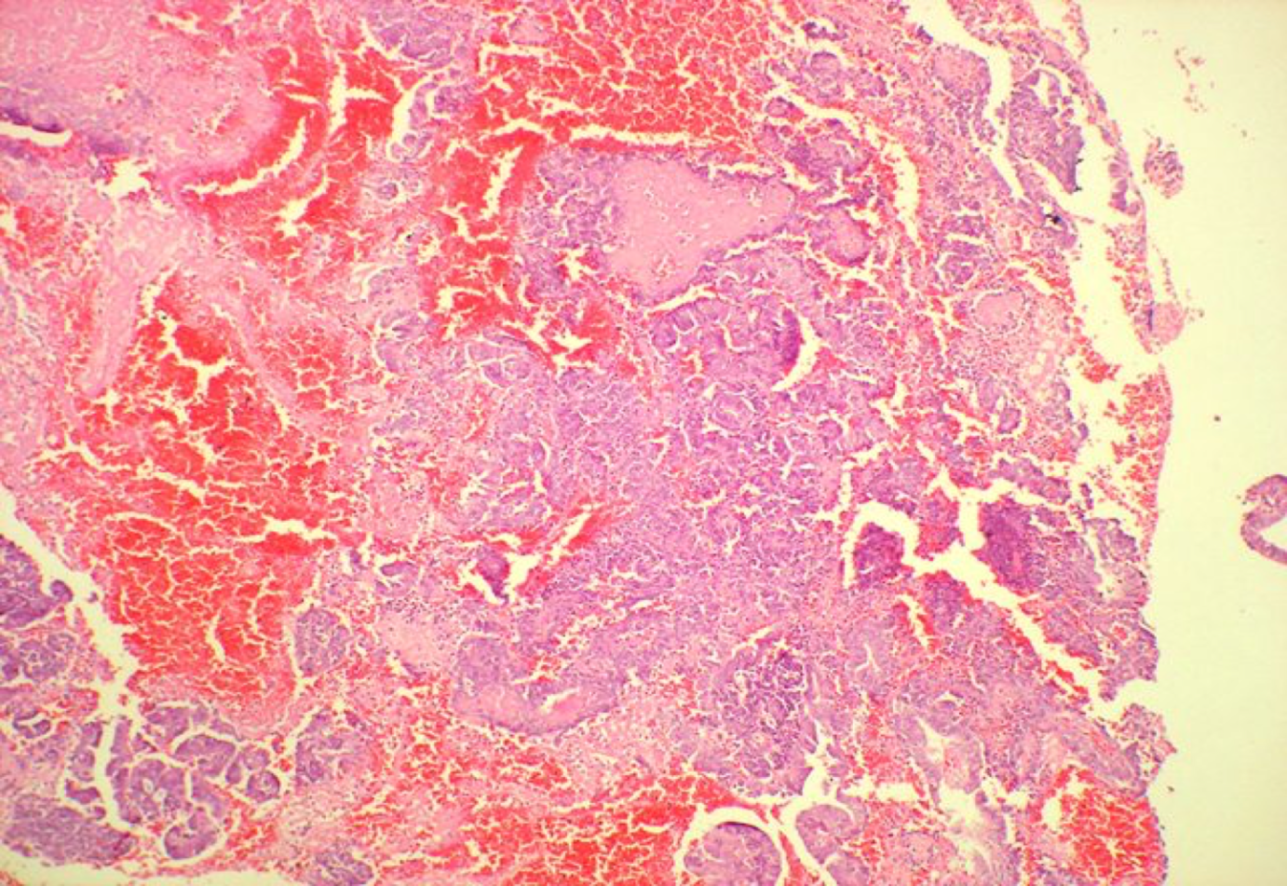

Deals with the various phases of Menstrual cycle and the morphological appearances of the same as seen in curettage material- early, mid, and late proliferative; day wise morphology of progesterone phase and IHC in normal endometrium.